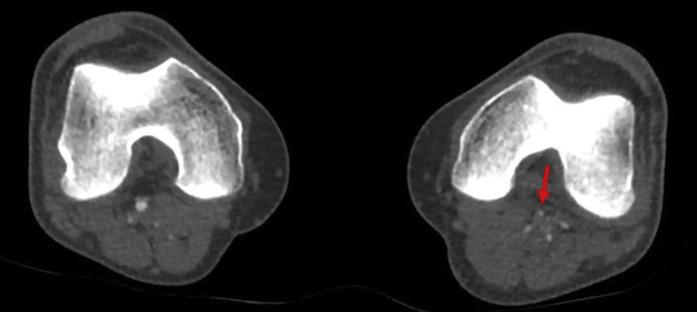

A 49-year-old man was admitted to his local hospital with left leg pain and breathing difficulties. He had negative nasopharyngeal polymerase chain reaction tests for severe acute respiratory syndrome coronavirus 2. Chest X-ray and Computed tomography pulmonary angiogram displayed typical coronavirus disease 2019 (COVID-19) radiological features as ground-glass opacities and bronchovascular thickening. His respiratory symptoms resolved after four days of supportive treatment, whereas his left leg became more painful and discolored. He was referred to our center with acute left leg ischemia. computed tomography angiogram revealed eccentric mural thrombus at the aortic bifurcation, extending into left common iliac and an abrupt occlusion of left popliteal, tibioperoneal, and posterior tibial arteries. He was treated with catheter-directed thrombolysis for 48-hours that achieved successful revascularization of the ischemic limb with no intervention-related complications. At six-week follow-up, he showed full recovery. Our case demonstrates that catheter-directed thrombolysis is a successful and safe treatment option in a COVID-19 patient with acute arterial occlusion.

一位 49 岁男性因左腿疼痛和呼吸困难入住当地医院。他的鼻咽聚合酶链反应检测严重急性呼吸综合征冠状病毒 2 呈阴性。胸部 X 光和计算机断层肺动脉造影显示出典型的 2019 年冠状病毒病(COVID-19)放射学特征,包括磨玻璃影和支气管血管增厚。经过四天的支持性治疗,他的呼吸症状得到缓解,但左腿变得更加疼痛和变色。他因急性左腿缺血被转至我们中心。计算机断层血管造影显示主动脉分叉处偏心性壁血栓形成,延伸至左侧髂总动脉,以及左侧腘动脉、胫前动脉和后胫动脉突然闭塞。他接受了 48 小时的导管定向溶栓治疗,实现了缺血肢体的成功再血管化,没有与干预相关的并发症。在 6 周的随访中,他完全康复。我们的病例表明,在 COVID-19 患者中,导管定向溶栓是一种成功且安全的治疗选择。